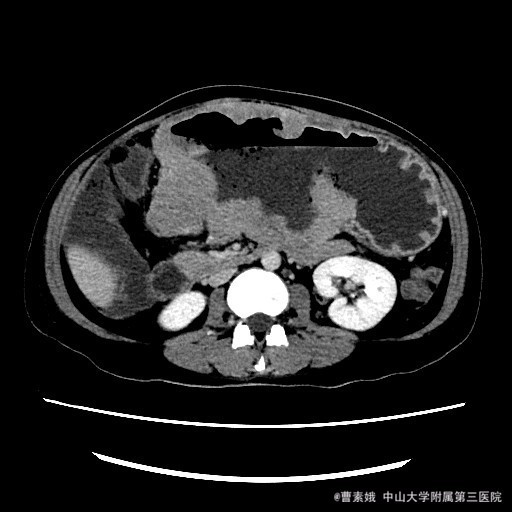

患者:女 37岁 主诉:发现腹部包块伴恶性、呕吐1月余 病史:患者平素一直有胃部不适,偶有胃痛、饱胀感不适,一直口服药物治疗,未见明显好转,1月前自觉腹部包块,并出现恶性、呕吐。呕吐为胃内容物。

查体:左上腹触及一包块,较柔软,余未特殊。 辅助检查:全腹CT平扫+增强示:胃体至胃窦部胃壁弥漫性增厚并软组织肿块,考虑淋巴瘤可能性大。

入院诊断:胃淋巴瘤(?) 治疗:诊断:胃淋巴瘤(?) 治疗:入院后(胃部肿物)送检组织镜下见胃粘膜固有层及肌层结构破坏,并见中等偏大异形淋巴样细胞弥漫浸润,局部成片分布,细胞具有异型性,可见核仁,核分裂象易见,结合免疫组化结果,符合高级别B细胞源性淋巴瘤,考虑滤泡淋巴瘤(FL3b)。组织少,肿瘤成份少,不完全排除弥漫大B细胞性淋巴瘤(生发中心亚型)。建议结合临床。排除手术禁忌症后,于腹腔镜下胃大部分切除术 。 术程顺利,患者恢复较好,建议其进一步化疗,患者表示拒绝后出院。